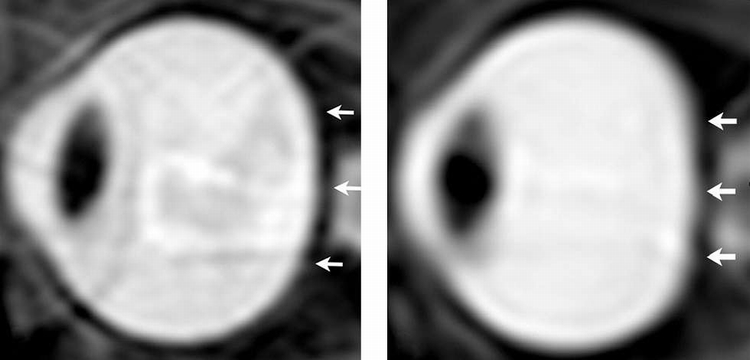

一张太空人眼睛的之前和之后MRI照片。

研究小组从7次长期任务和9次短期任务的太空人的眼部,进行任务前和任务后的高解析度MRI扫描。

相较于短时间任务的太空人,长时间任务的太空人眼睛的平坦度增加,而且眼球后方有较高含量的CSF。分析也显示,CSF含量越高,观察到的变形就越大。